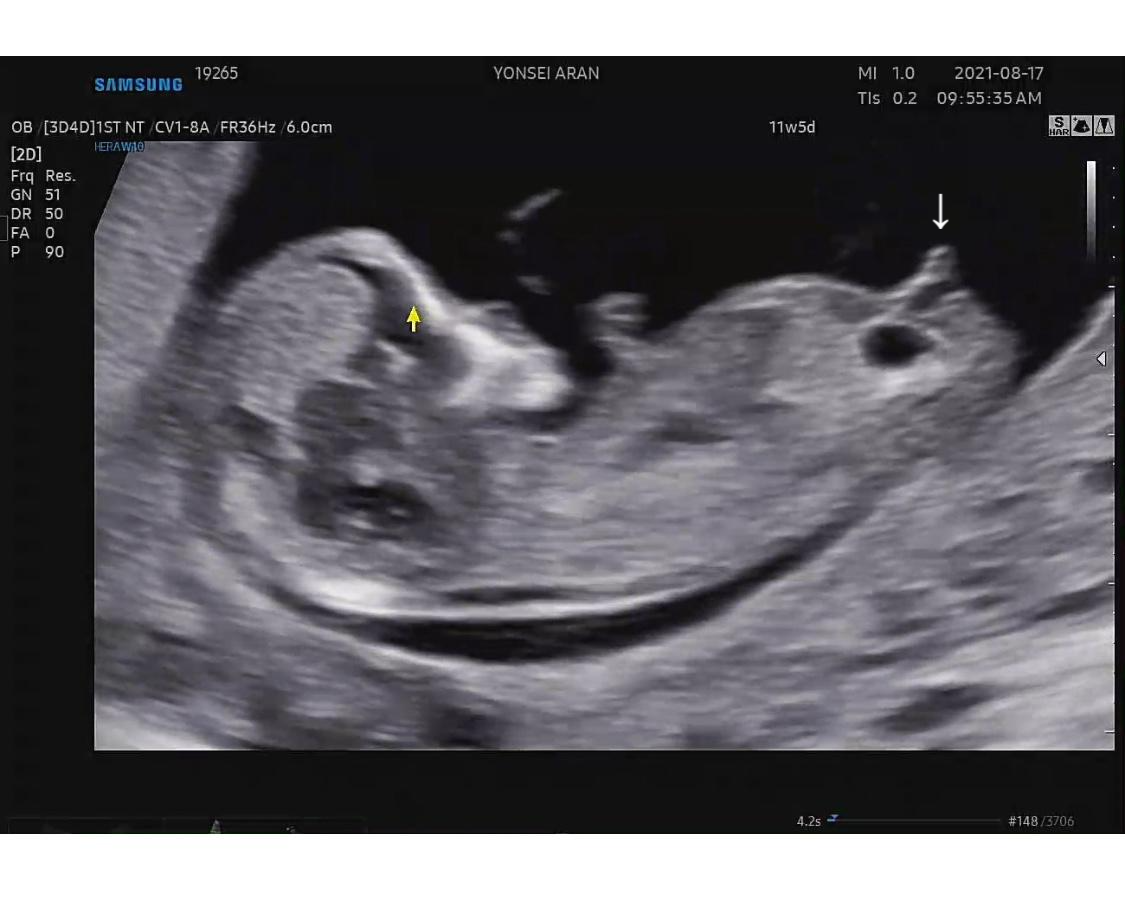

각도법

11주 5일 초음파를 보러갔다.

이 때 받은 초음파 영상을 분석해서 아들이 아닐까 추측하게 되었다.

처음에는 각도법도 난황법이나 떠도는 각종 성별을 알아보는 법처럼 부정확한건줄 알았는데

나름 신뢰도가 높은 것 같았다.

외성기(NUB)와 척추뼈(SPINE)의 각도를 보는건데

각도가 수평이면 여아고

30도 이상이면 남아라는데..

우리 포도는 아무리봐도 수평은 아닌 것 같았다.